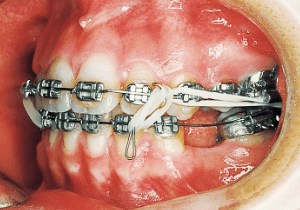

Congenital missing tooth

8 3-23-’87 Treatment Progress

The treatment progressed more favorably than anticipated, with the open bite and Class II malocclusion nearly resolved within five months of treatment initiation. However, discontinuing the use of rubber bands often resulted in an open bite.